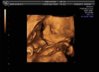

U nas po wczorajszej wizycie też same dobre wieści. Mała rośnie i fika! Waży już 440g.